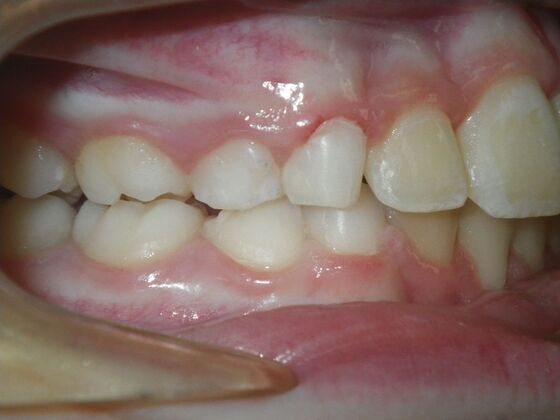

This sweet patient presented with constricted upper and lower arches and blocked out, rotated upper and lower anterior teeth. The upper centrals were leaning backward and had the lower arch captured preventing anterior advancement. Treatment was begun on the upper arch first, followed with placement of lower lip bumper to allow for lateral and anterior development of lower arch. Eventually placed lower brackets with strategic slenderizing of primary teeth to allow permanent incisor to assume their proper placement. All accomplished within 12 months and straight-wire appliances.